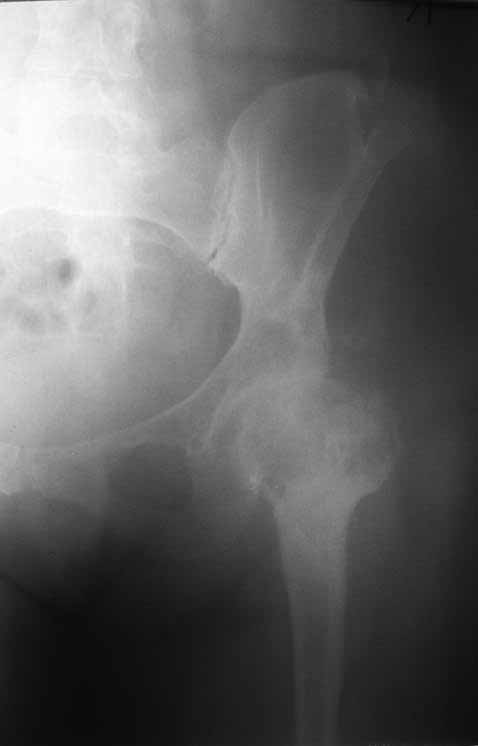

Уважаемые коллеги. Хотелось бы услышать мнения и советы по представляемому случаю. Пациентка 45 лет. Бесцементное эндопротезирование левого тазобедренного сустава 6 лет назад (впадина RM, Mathys, металл-металл, ножка Зульцеровская). За 10 лет до протезирования – коррегирующая остеотомия бедренной кости, которая не срослась в течение года до удаления пластины, а затем срослась в течение 3 месяцев иммобилизации в кокситной повязке. После протезирования получилось наблюдать пациентку почти постоянно, поскольку через 2 года синтезировал ей лодыжки на оперированной стороне, затем, через несколько месяцев удалил фиксаторы, а в 2009г. резецировал мениск на противоположной стороне. Боли все эти годы не беспокоили. Пациентка чуть выше среднего роста, вес тела нормальный. Физические нагрузки переносила хорошо. Работает на 7 этаже без лифта. Год назад экстирпация матки по поводу лейомиомы больших размеров. Несколько месяцев назад появились боли в области левого тазобедренного сустава. При рентгеновском и КТ исследованиях (июль с.г.) – нестабильность тазового компонента. От предложенной замены протеза пациентка на тот момент, слава богу, отказалась. Через какое то время боли в области левого тазобедренного сустава практически полностью прошли, а около 2 месяцев назад появилось ощущение патологической подвижности таза и боли в паху справа, которые через некоторое время уменьшились, а потом снова усилились после значительных физических нагрузок (много ходила по песку на пляже, носила тяжести). Ежедневно принимала диклофенак. На рентгенограммах – переломы правой лонной кости. Сейчас госпитализирована из-за болей в паху справа. Боли слева не беспокоят. На фоне снижения нагрузок в стационаре боли значимо уменьшились. Способна ходить без средств дополнительной опоры.В анализах крови чуть повышены трансаминазы и гамма-ГТ, моча без особенностей.

Вопросы: -правильно ли я расцениваю переломы как стрессовые на фоне неполноценного таза (pelvic insufficiency stress fractures)? -Можно ли так же расценить ситуацию на стороне протеза и, соответственно, не торопиться с ревизией, рассчитывая на вторичную стабилизацию? Уж больно не хочется менять ножку. -Если думать о ревизии, то когда? На представленных снимках тазобедренный сустав до и сразу после операции, затем 2 снимка 2009г., когда ничего не беспокоило, затем КТ 2-х месячной давности и вчерашние рентгенограммы обоих тазобедренных суставов.

Сергей, очень возможно, что перелом и стрессовый, но мне видится, что его причина в нестабильности чашки. Дело в том, что в отличии от ножек, чашка при своей дестабилизации болит гораздо меньше и больные терпят до последнего.

При сравнении рентгенограмм можно увидеть насколько чашка переместилась от места своего первичного расположения. От опрокидывания ее удерживают конструкционные элементы "рожки". Без них ситуация, возможно, уже была бы катастрофической (чашка в тазу). Думаю надежды на вторичную интеграцию, могут быть обмануты и ревизии не избежать.